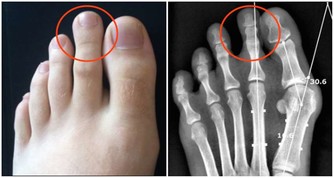

2.莫名出現血壓升高的現象

要知道,在臨床上,有一種叫做腎病高血壓的並發症。而對於男性來說,若是發現自己的血壓莫名地開始升高時,那就需要注意了,這或許是腎臟受損,導致體內的鈉離子代謝異常,和電解質失衡的表現。

若是這種症狀不引起重視,任其發展,最終可能會引起全身性的血壓紊亂,從而給身體帶來嚴重損傷。 文章來源: /c/user/token/MS4wLjABAAAAwhEarYBZfWlcY2qOqDOy5DH8QVcnyNQ5hUQtXfWGNsY/?source=tuwen_detail